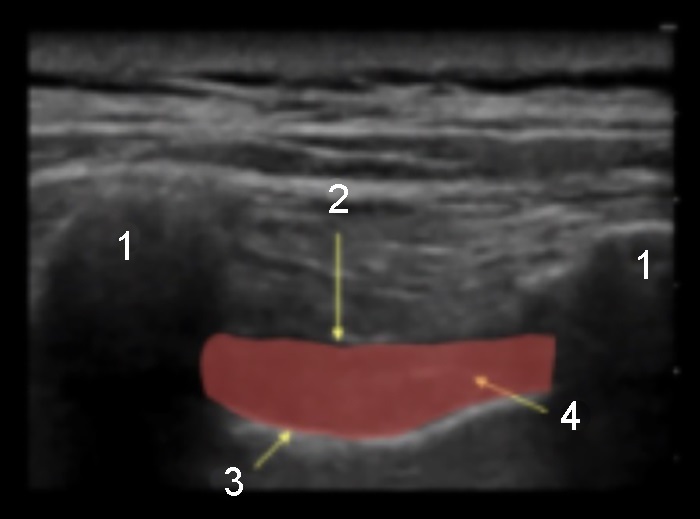

傍脊椎注射後傍観的アプローチの画像

横断プロセス

肋横突靭帯

胸部

傍脊椎腔